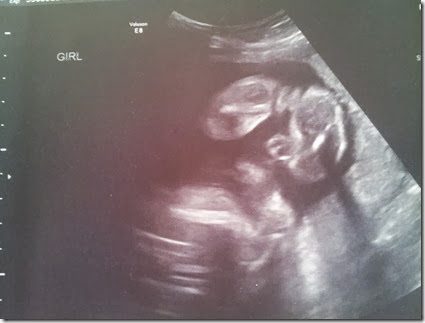

A few weeks ago we had our big ultra sound at Mckay Dee Hospital to make sure everything was looking good! Our doctor sent us to the hospital this time around since Dakota was born with a heart defect so that they could look even closer to make sure the same thing wasn’t going on.

BUT it was such a relief to see all of HER little body parts and organs moving and working just as perfectly as they should be. They did say that if she had Dakota’s same heart condition (which it isn’t genetic so the chances are slim to none) that it could show up later on BUT as for right now it was beating perfectly normal!! We couldn’t have been any happier and I left with such a huge smile on my face!

I was also of course excited for them to point out her little girly parts so I can know for sure it is a GIRL!!!

These ultra sound pictures are still so unreal to me! It is crazy how much they can see. They still look a little alienish to me but I think she is just adorable already!! She had her cute little arms up by her face most of the time so this is the best we got!